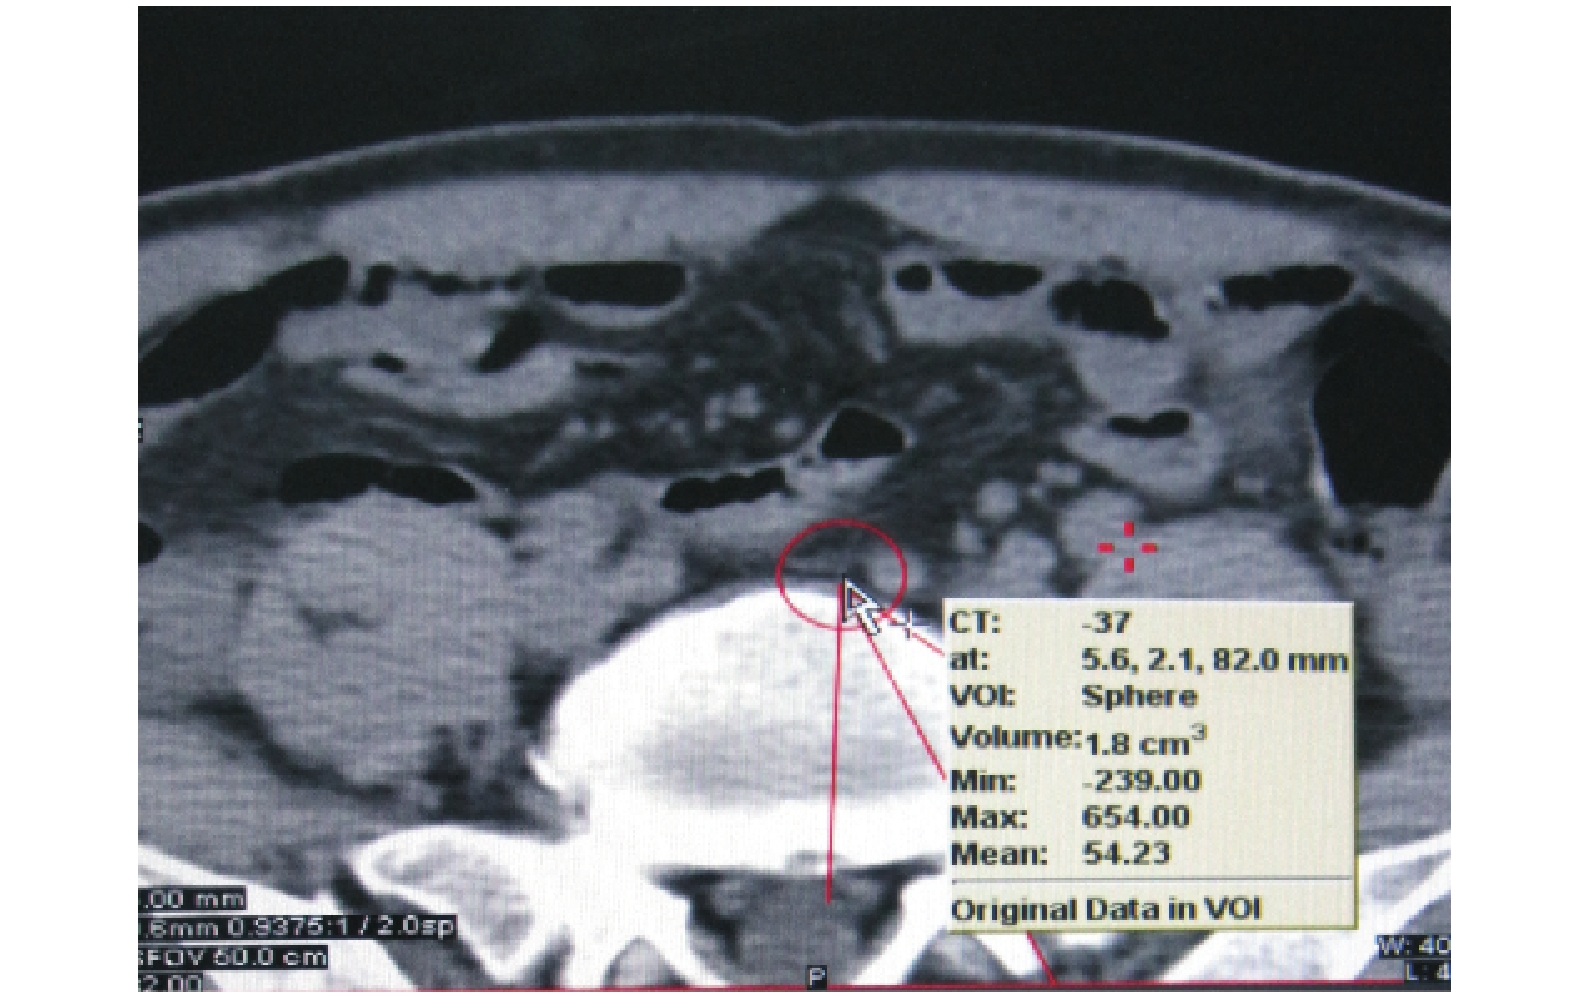

本研究所采用的 SLN 示蹤劑由 1.0 mL 放射劑量為 17.5~37.0 mBq 的 99Tcm-sc 與 1.0 mL 納米炭混懸注射液混合而成。采用“三明治”注射方法(生理鹽水-淋巴結示蹤劑-生理鹽水)于術前 1 d 經內鏡將淋巴結示蹤劑分 4~6 個點注射于距原發腫瘤邊緣約 1 cm 的正常黏膜下層(圖 1)。在注射后的第 1、3 及 5 小時分別行 SPECT/CT 掃描,分析區域淋巴結狀態(圖 2)。所有結腸癌患者接受結腸全系膜切除手術治療,若腫瘤供血血管來自腸系膜上動脈行根治性右半結腸切除術,若腫瘤供血血管來自腸系膜下動脈則行根治性左半結腸切除術或根治性乙狀結腸切除術,并按腫瘤學要求徹底清掃所有腫瘤區域的淋巴結。這種手術方式清掃了存在于筋膜和系膜之間的腫瘤周圍和引流區域的淋巴結,以及腫瘤細胞可能轉移擴散的腫瘤供血血管周圍淋巴結。術中尋找納米炭黑染的 SLN(圖 3),判斷 SLN 并指導術中淋巴結清掃。術后標本中清掃的淋巴結按腸旁、中間和主淋巴結分類。用 γ 放射免疫計數器測量術前 SPECT/CT 顯示的 SLN 區域內的淋巴結,取放射性計數值最高(放射活性超過背景 10 倍以上)的 1 枚或者幾枚淋巴結確定為 SLN。